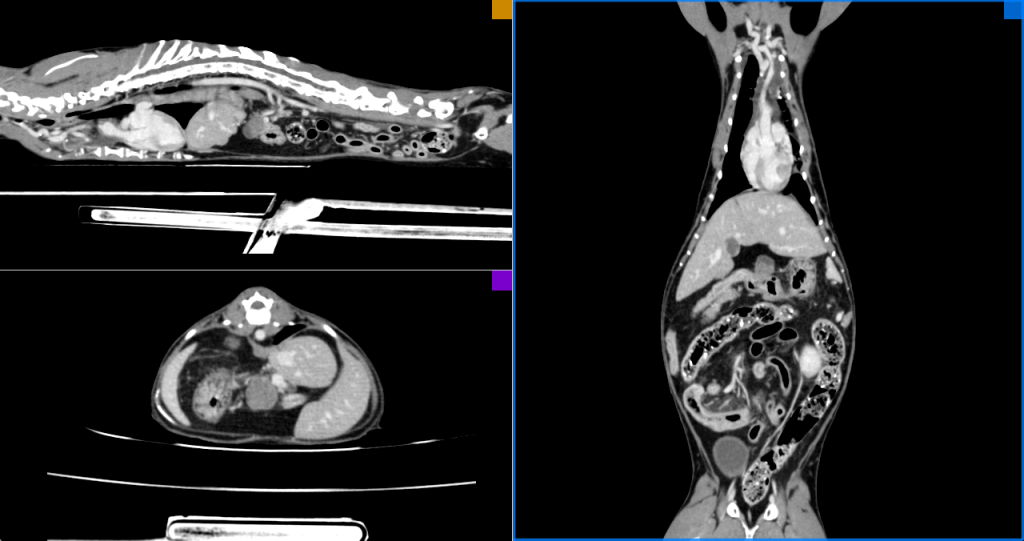

Спустя 6 месяцев с момента проведения компьютерной томографии в момент обращения была проведена контрольная неселективная КТ-ангиография (рис. 4).

В первый месяц терапии наблюдались признаки частичного ответа (PR), а на всех последующих циклах – признаки полного ответа (CR). Это сопровождалось хорошим качеством жизни питомца, и владельцы отказались от перехода на химиотерапию по протоколу COP, поэтому им было предложено продолжить терапию без ограничения по времени после 12-й инъекции пегаспаргазы (Oncaspar®; Les Laboratoires Servier).

Перед каждой процедурой дачи ломустина проводился общий клинический анализ крови, а также осуществлялся постоянный ультразвуковой контроль брюшной полости для мониторинга рецидива и при необходимости – в случае ухудшения аппетита или других нарушений общего состояния пациента. При появлении негативных реакций со стороны организма, связанных с противоопухолевой терапией, также осуществлялся ультразвуковой мониторинг и дополнительно проводился ОАК. Контрольное рентгенологическое исследование не проводилось. Спустя 6 месяцев после начала терапии (в состоянии клинической ремиссии и полного клинического ответа) было выполнено контрольное КТ-исследование.